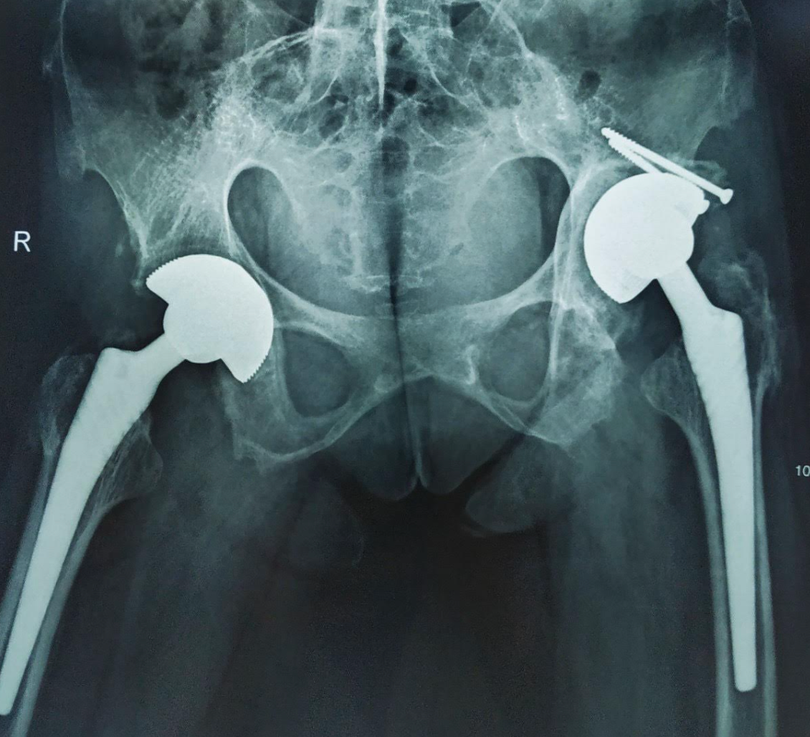

| Hình ảnh X-quang khớp háng của bệnh nhân (Ảnh - BVCC) |

BS. Toàn cho biết ca mổ của chị H là một ca mổ vô cùng phức tạp vì cả hai khớp háng đã có biến chứng viêm dính biến dạng và xuất hiện tình trạng viêm trong máu thường xuyên ở mức cao dễ dẫn đến chậm liền vết thương, thậm chí nhiễm trùng sau mổ. Trước tình trạng của chị, các bác sĩ đã hội chẩn đa chuyên khoa kỹ lưỡng và đưa đến quyết định mổ thay khớp háng 2 bên bằng kỹ thuật mổ ít xâm lấn với khớp hai chuyển động chống trật và chống mài mòn.

Các phương pháp điều trị chỉ có thể cải thiện triệu chứng và ngăn ngừa bệnh trở nên xấu đi. Phẫu thuật thay khớp háng: chỉ định trong trường hợp bệnh nhân đau kéo dài, hạn chế vận động và có phá hủy cấu trúc rõ trên hình ảnh X-quang. Phẫu thuật chỉnh hình đối với cột sống: chỉ định khi cột sống biến dạng.